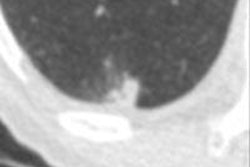

- Finding suspicious nodules in the range of 5 mm to 25 mm in diameter

Developing a CAD algorithm for tomosynthesis presents a number of challenges, as tomo images fall somewhere in appearance between x-ray and CT, the researchers noted. Tomo systems create slices like CT systems do, but slice thicknesses are much larger.

In a series of 27 tomosynthesis scans performed on patients at Semmelweis University, the researchers found sensitivity of 70% to 90% for nodules 3 mm to 7 mm, with one false-positive detection per tomo slice. They concluded that this was far too many false positives, so they are considering the development of new algorithms.

With respect to measuring nodule volume, the researchers noted that this is an important task, as nodule growth over time can help distinguish between aggressive and slow-growing cancers. Their CAD algorithm struggled in measuring lesion doubling time in nodules smaller than 6 mm.